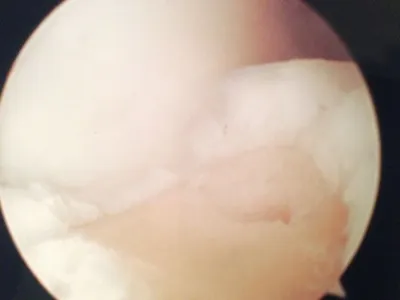

Pic of an OCD in the talar dome due to pressure from the nodule.